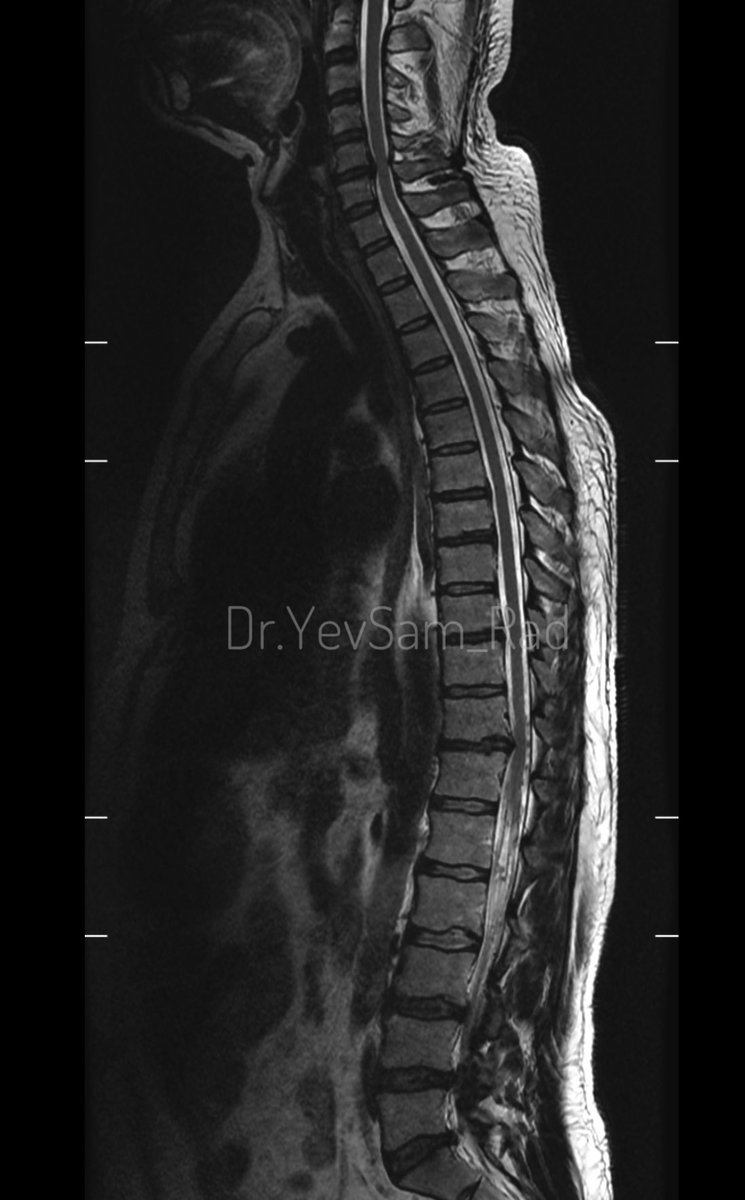

Young gentleman came with severe low back ache following an episode of dengue fever. What do we see here? #spineimaging #medtwitter #radtwitter #FOAMrad #neuroimaging @drvenkimdrd

DrYevSam_Rad's tweet image. Young gentleman came with severe low back ache following an episode of dengue fever. What do we see here?